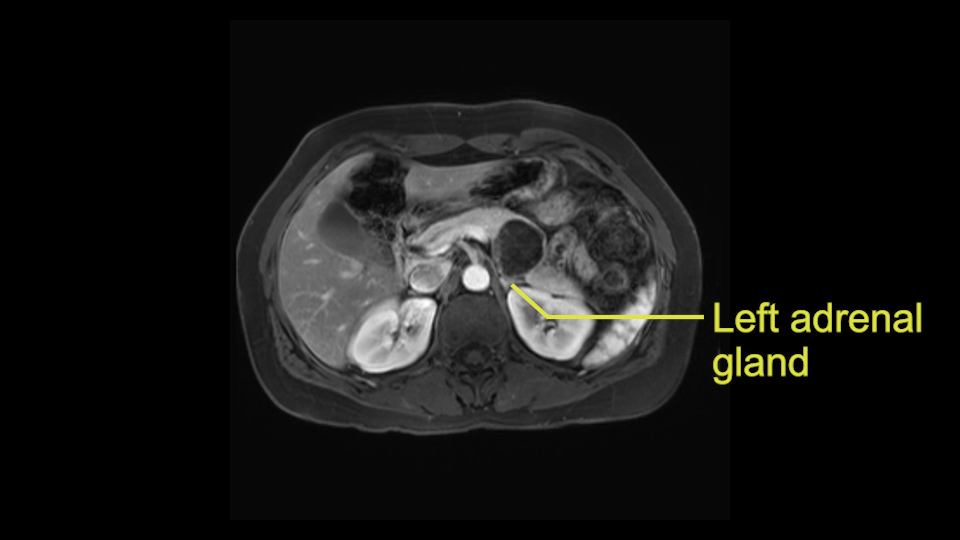

Tumor proximity to left adrenal gland

The lesion also is quite posterior. While the plane between the cyst and the left adrenal gland is often preserved, we do have to pay attention here so that we remain in the right plane and maintain our margin here. Occasionally in these cases, en bloc adrenalectomy needs to be performed.

Sometimes with even benign lesions of the spleen you can have quite a lot of inflammation in the retroperitoneum and so I do think about and wonder whether I will have some difficulty in the retroperitoneum and I usually look at the scan for that purpose. It looks like there is no inflammation in the retroperitoneum. It does look very close to the patient’s left adrenal gland but knowing the planes and suspecting that there isn’t any active inflammation, this should be able to come off the left adrenal gland without any difficulty. But obviously prepared to take some of the left adrenal if that’s necessary in this procedure. So those are my procedure-specific slowing down moments in a distal pancreatectomy when I’m considering a laparoscopic approach. I think the patient-specific slowing down moments in this particular case I have discussed with the procedure-specific moments. I don’t really see any other issue or that I have to be careful of or consider.

So first, I'll show you the scan. Here's the traditional view, where you see the cyst, which is in the body of the pancreas. And you see over here, it's got a quite thick wall. And going a little bit back also, here you see a septation which is very important, because I think a septation is what separates this from, for instance, the pseudocyst of the pancreatitis. And also the location of the cyst you see here, abutting the adrenal gland and going down a bit more, it's also quite close to a bowel loop. So when thinking about this cyst: female, the location in the body of the pancreas, thick wall, septation, and as you can read in history, it was basically asymptomatic, so no signs of pancreatitis. So, this probably all points towards a mucinous cystic neoplasm.

So what I would normally do in these patients, I would look at the abutment of any other organs, one, which is here, potentially the adrenal gland and two the small bowel. And two, look at the distance from the vessels which I would normally do in a coronal view. So you can easily measure the distance and third I look at the insertion of the inferior mesenteric vein. Now we can probably also see that on here. Although it's better on a CT scan and it's better on a coronal view, you want to know where the inferior mesenteric vein comes into either the splenic or the SMV, because that is typically a very important slow down moment when you mobilize the lower portion of the pancreas knowing where the inferior mesenteric vein comes in either the splenic vein or the SMV. So those are I think the three most important points for the CT scan.

After you've slung the pancreas, to the left of the cyst, and if you encounter any adrenal involvement later after you have transected the pancreas and you move to the left side of the patient towards the spleen, take either the entire or partial left adrenal gland with the resection. If you go underneath the adrenal gland, and it's probably best to do a full RAMPS (Radical Antegrade Modular Pancreatosplenectomy) procedure, that is where you take the Gerota’s fascia completely onto the mucinous cyst. And that's very crucial to get a radical resection if you think the adrenal gland is involved.